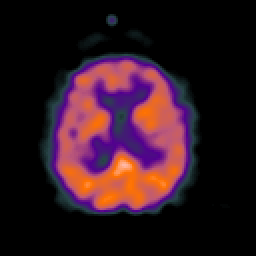

Normal aging, overlay -- Slice #33

[Home][Help][Clinical] Slice 33